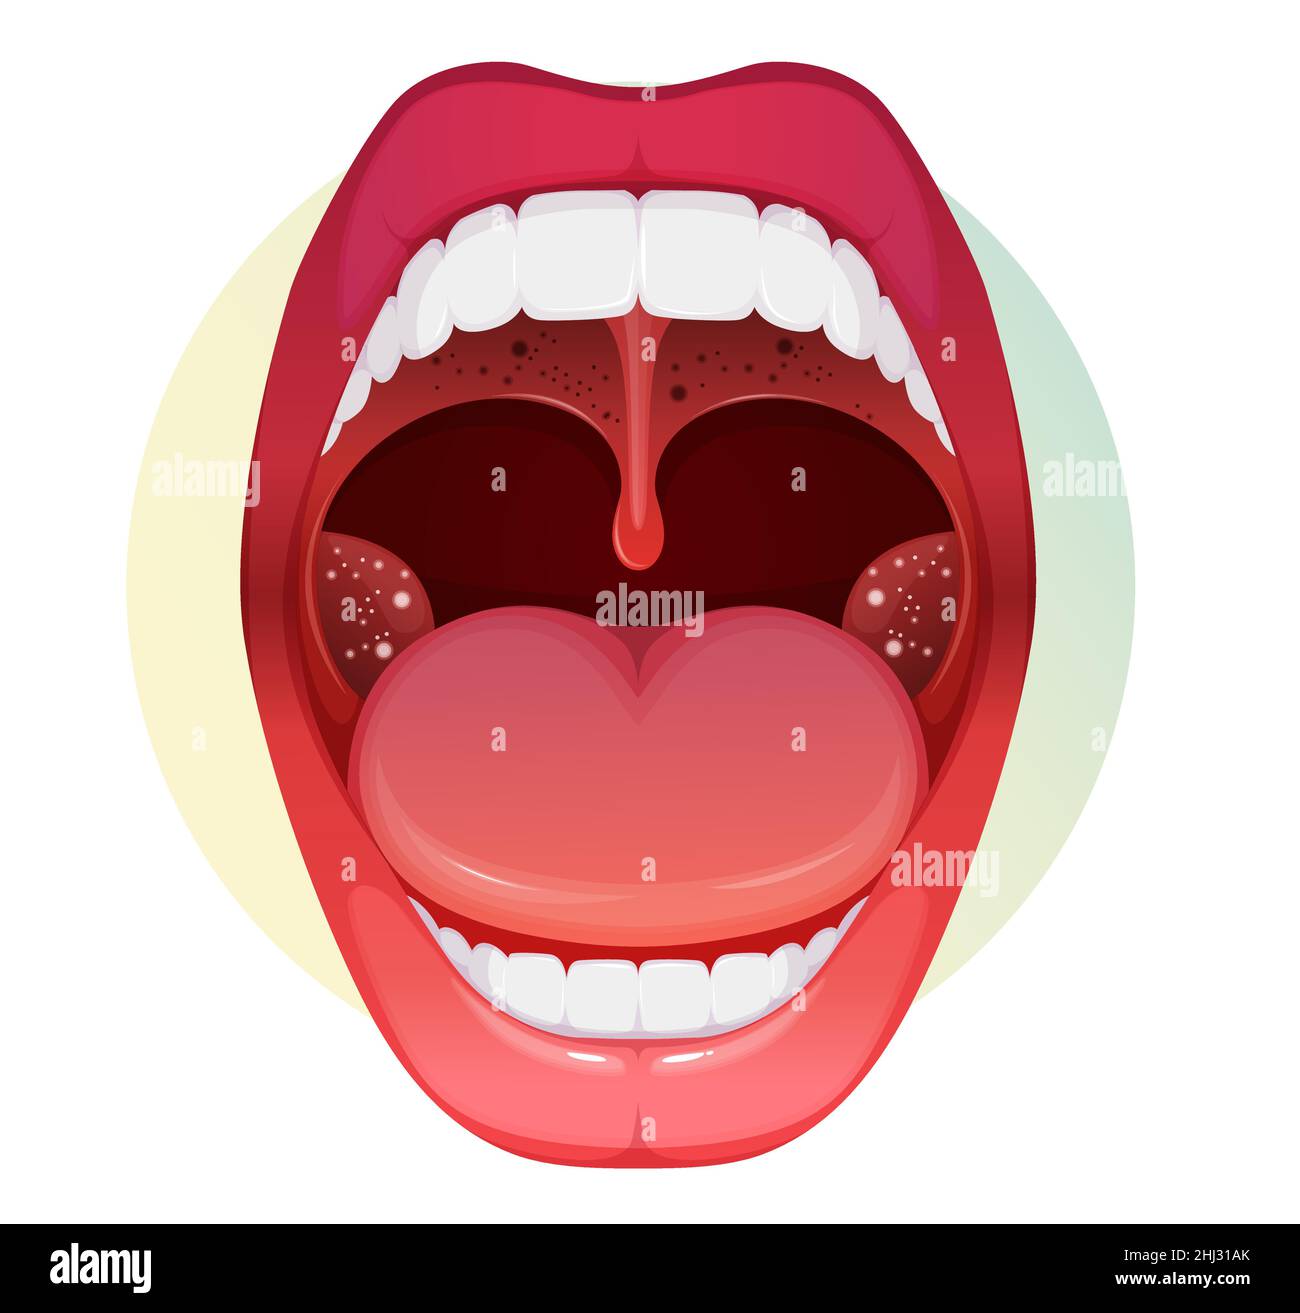

Offener Mund mit Halsschmerzen und Mandelentzündung - Stock Illustration als EPS 10 Datei Stock Vektorhttps://www.alamy.de/image-license-details/?v=1https://www.alamy.de/offener-mund-mit-halsschmerzen-und-mandelentzundung-stock-illustration-als-eps-10-datei-image458600315.html

Offener Mund mit Halsschmerzen und Mandelentzündung - Stock Illustration als EPS 10 Datei Stock Vektorhttps://www.alamy.de/image-license-details/?v=1https://www.alamy.de/offener-mund-mit-halsschmerzen-und-mandelentzundung-stock-illustration-als-eps-10-datei-image458600315.htmlRF2HJ31AK–Offener Mund mit Halsschmerzen und Mandelentzündung - Stock Illustration als EPS 10 Datei